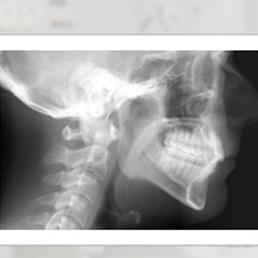

A skull X-ray is used to evaluate the patient's occlusion and take the measurements necessary for selecting dental braces.

- Cephalometric X-ray (cephalometry) – used in orthodontics. It shows the skull profile and the position of the teeth relative to the craniofacial bone structure. One of the fundamental tests in planning malocclusion treatment.